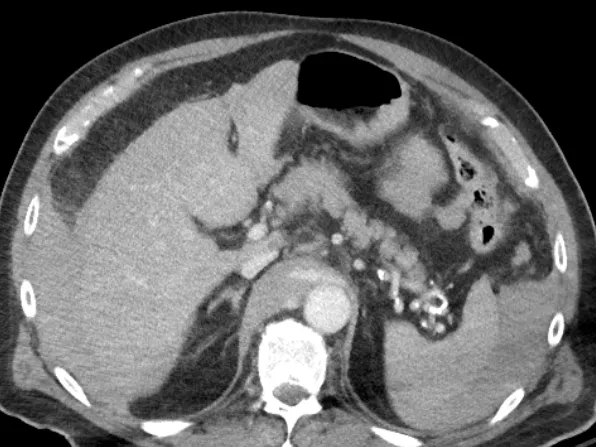

Join Dr Fausto Labruto as he gives an overview of the diagnosis of abdominal trauma. This 3-day case-based online emergency radiology course will consist of a mix of lectures, individual case reading, and group case discussions. 📅 Select your preferred dates below - the same comprehensive 3-day course is offered on both date options for your convenience.

This emergency radiology fellowship course of 3 half days includes an overview of the main mechanisms of injury, examination trauma CT protocols , reading techniques with tips and tricks and reporting guidelines including the injury scoring scale of the American Association for the Surgery of Trauma (AAST).